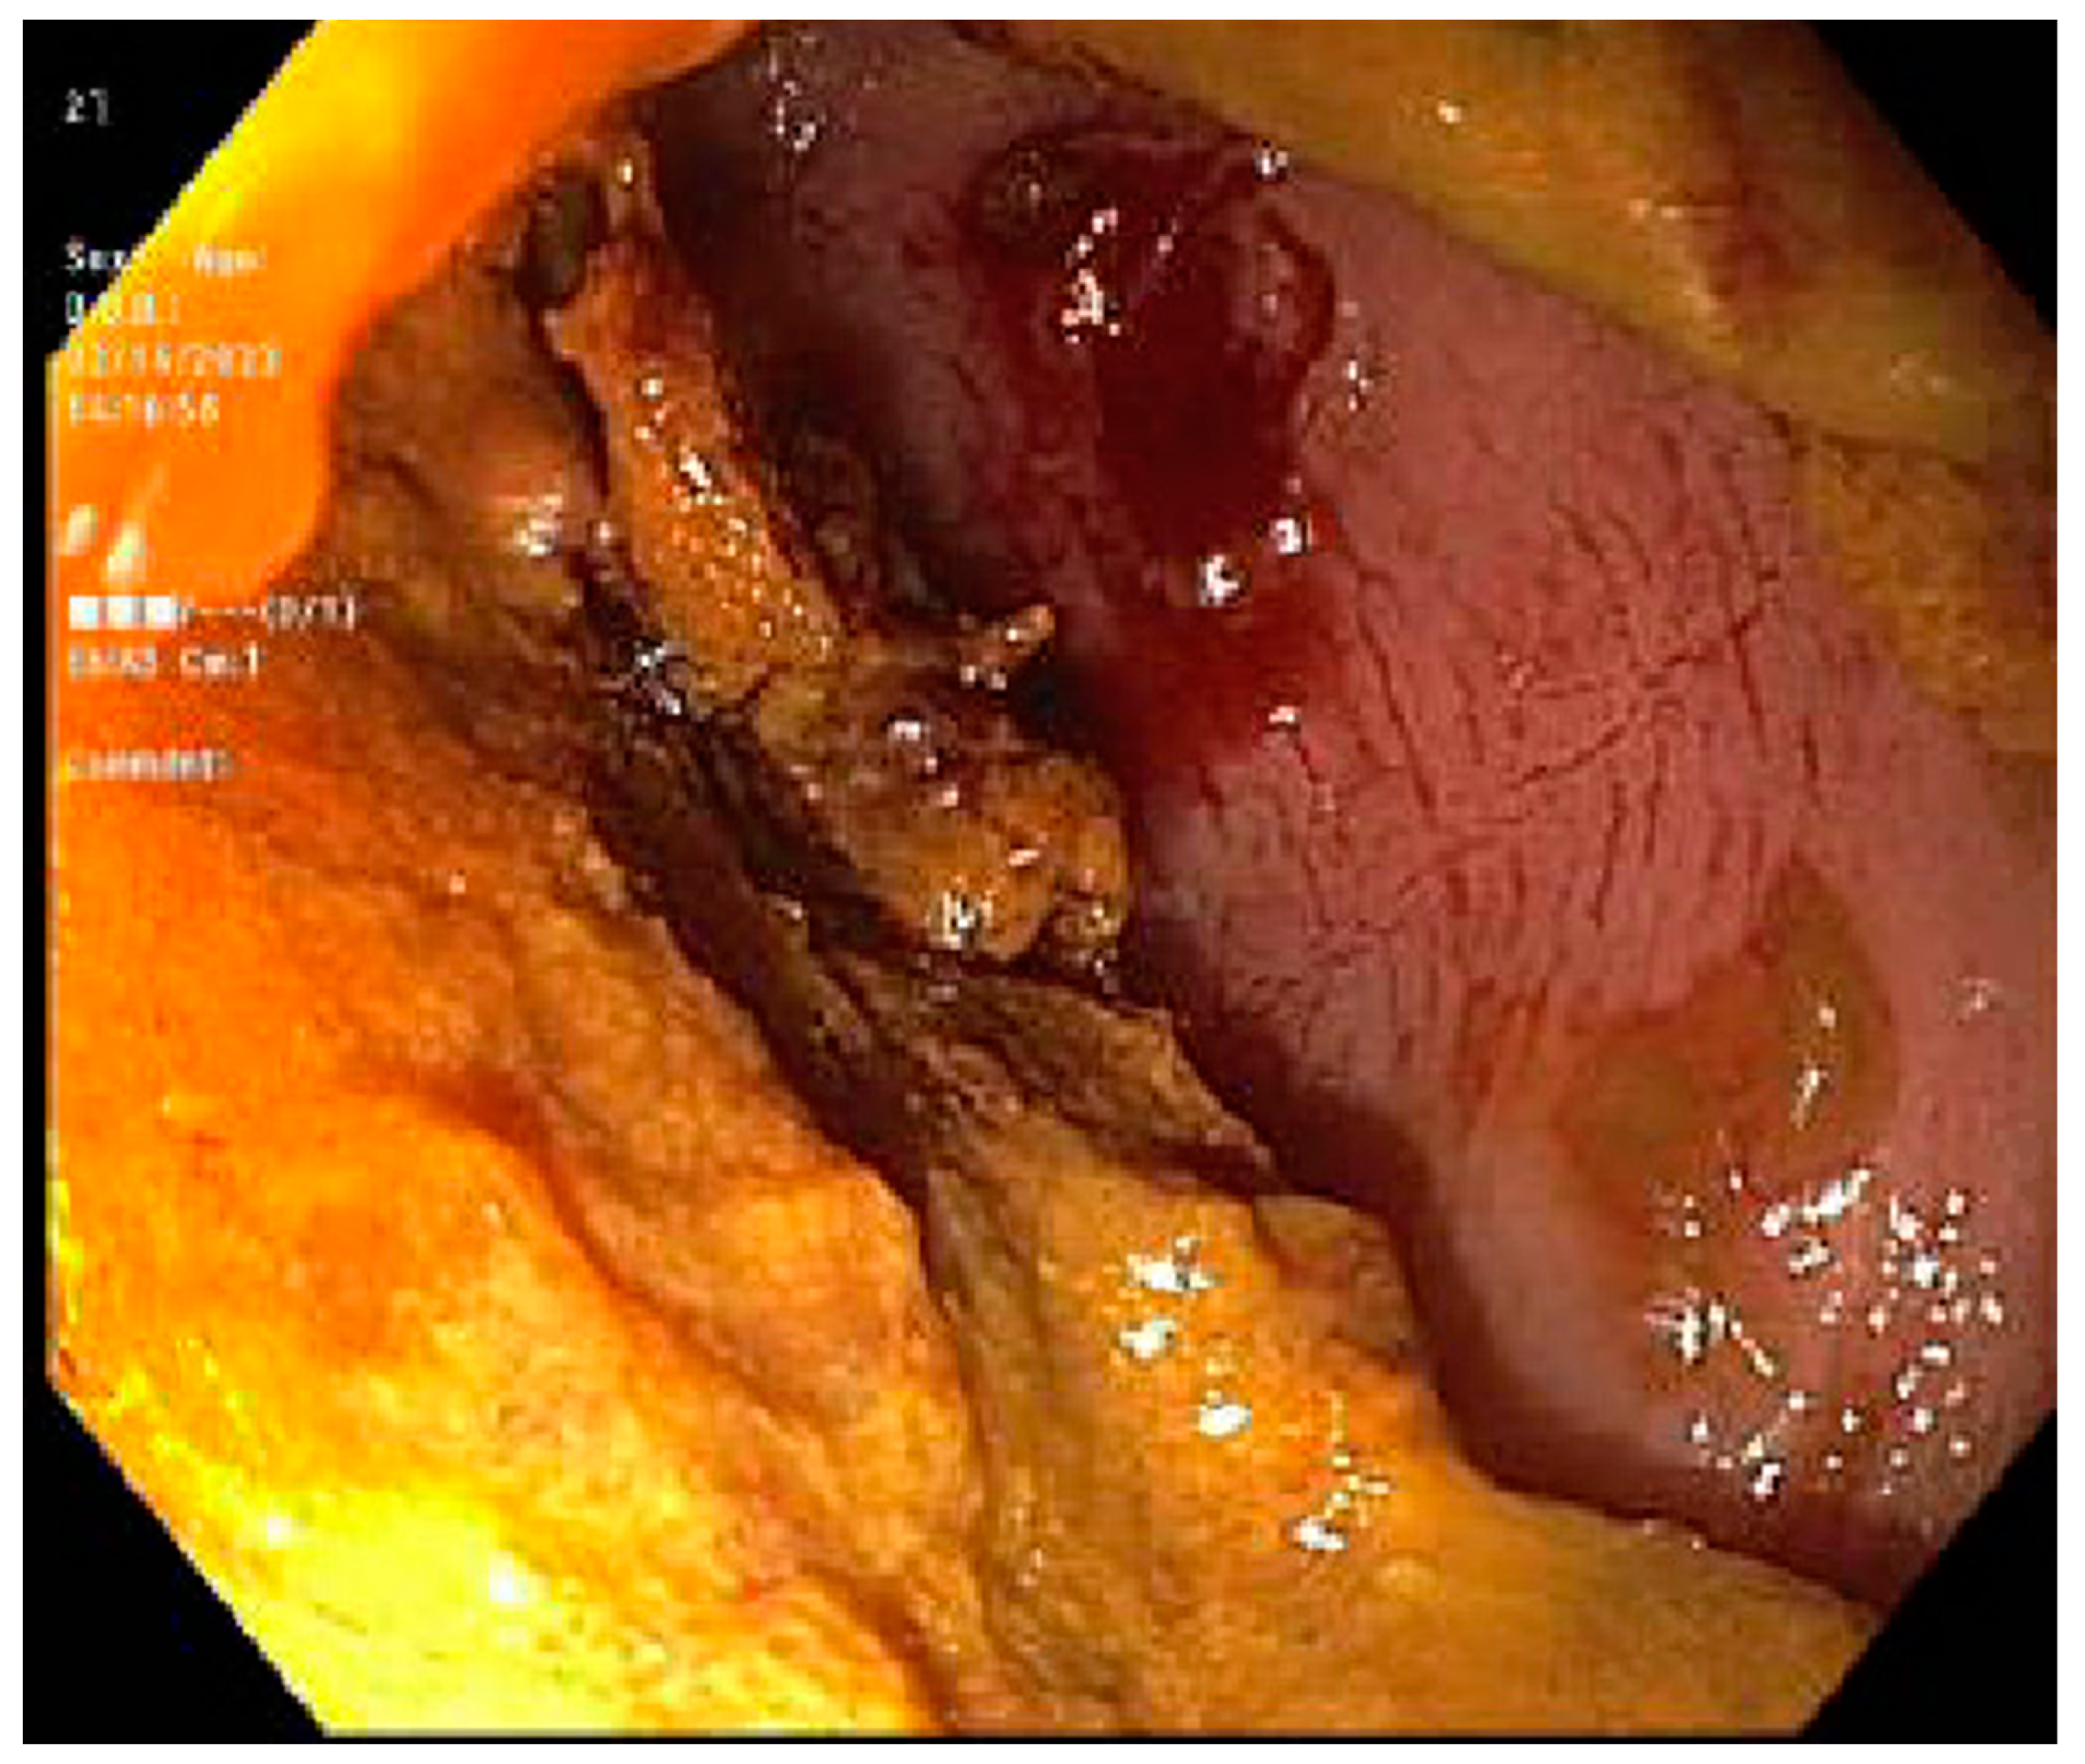

- Cruz-Correa, M.; Poonawala, A.; Abraham, S.C.; Wu, T.T.; Zahurak, M.; Vogelsang, G.; Kalloo, A.N.; Lee, L.A. Endoscopic findings predict the histologic diagnosis in gastrointestinal graft-versus-host disease. Endoscopy 2002, 34, 808–813. [Google Scholar] [CrossRef]

- Oomori, S.; Takagi, S.; Kikuchi, T.; Utsunomiya, K.; Yokoyama, H.; Negoro, K.; Tohmiya, Y.; Aihara, H.; Yamada, M.; Takahashi, S.; et al. Significance of Colonoscopy in Patients with Intestinal Graft-Versus-Host Disease after Hematopoietic Stem Cell Transplantation. Endoscopy 2005, 37, 346–350. [Google Scholar] [CrossRef] [PubMed]